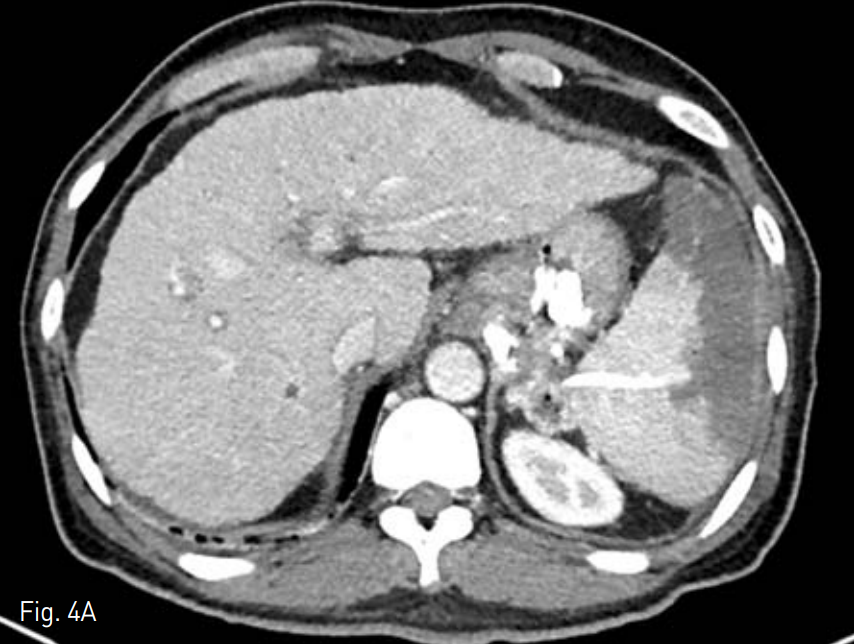

조영증강 전산화 단층촬영술 상 위 기저부에 정맥류 차단술을 시행한 것이 관찰되며 이와 이어지면서 좌측 전방 신 주위 공간에 4cm 크기의 농양이 관찰되었다(Fig. 1A, B).

Contrast enhanced axial (A) and coronal (B) CT scan shows 4cm sized abscess at left anterior pararenal space.